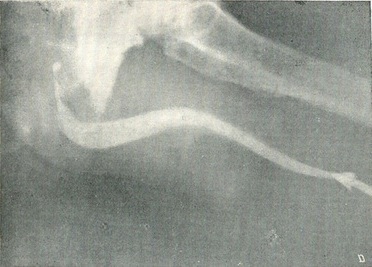

Ангіографія нирок. Діагностика захворювань нирок у деяких випадках може бути уточнена шляхом серійної ниркової ангіографії. Контрастна рідина - 70% розчин трийотраста або кардиотраста в кількості 30 мл - вводиться в аорту шляхом транслюмбальной пункції її або через поліетиленовий катетер, ретроградно введений в аорту через оголену гілка стегнової артерії (a. profunda femoris) або шляхом черезшкірної пункції стегнової артерії (по Сельдінгеру). Введення контрастної рідини і знімки повинні проводитися з великою швидкістю (не менше 3 знімків в секунду).

Перший знімок проводиться в кінці введення контрастного розчину, чергові 2-3 знімка - протягом наступної секунди. На першому знімку - артериограмме - виходить зображення судинної мережі нирки (рис. 41), на другому і третьому - нефрограммах, - крім цього, видно і тіні нирки, дифузно насиченою контрастним речовиною, на більш пізніх - зображення чашково-мискової системи і сечоводу - урограмма.

Рис. 41. Транслюмбальная ангіографія нирок. Нормальна ангіограма. Судинна фаза.